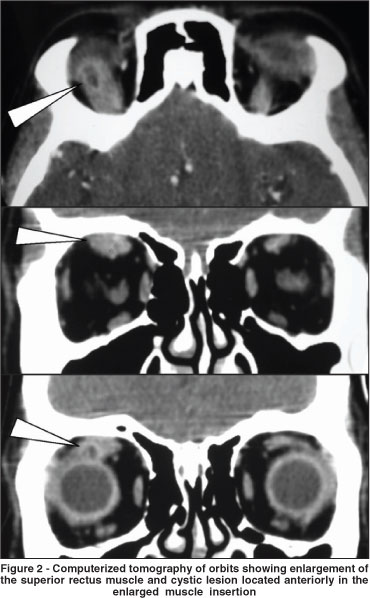

Because of the atypical restriction on downgaze and unresponsiveness to corticosteroid treatment, imaging studies were reviewed. Computerized tomography (CT) scans disclosed a small cystic round lesion associated with a marked superior rectus muscle enlargement that had been present in two previous CT scans but had been overlooked (Figures 1 and 2). No other abnormalities were found on imaging or laboratory investigations. An excision biopsy was indicated and carried out through a right upper fornice conjunctival incision. At surgery a cyst was found near the insertion of the superior rectus muscle. Its mucoid content and capsule were sent to histopathological study that confirmed the diagnosis of cysticercosis infection. A parasitologic examination was negative, and oral steroids were gradually tapered and removed. Right eye restriction improved partially, remaining a 20 diopter right hypertropia with a 15 diopter exotropia when fixing the left eye in Prisma and Cover Test.

Imaging studies such as B scan ultrasonography, magnetic resonance imaging and CT scan can be helpful especially when a cystic formation or calcification inside the muscle is documented. Such findings however, may be very discrete and overshadowed by the marked enlargement of the muscle, usually extending far beyond the cyst, as it occurred in our case (Figures 1 and 2).